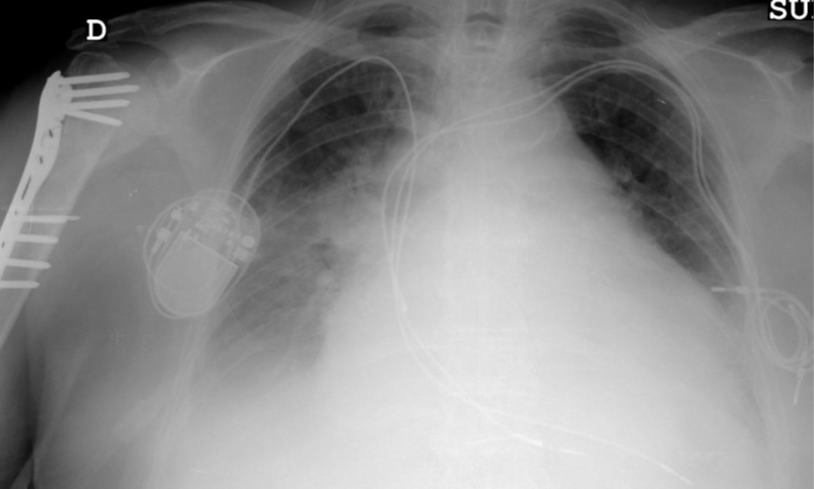

El viernes se analizarán las infecciones en dispositivos cardíacos y neuroquirúrgicos, y a continuación se celebrará una mesa redonda sobre infecciones complejas en pacientes inmunocomprometidos.